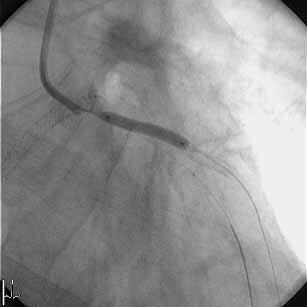

�͂��߂܂��āB���A�r58�N���̒��N��t�ł��B���͂܂��sRA�ł̃C���^�[�x���V����

�͖��o���ł��B�����~���L�b�g���łĂ���A�܂����ꂽfemoral�ł�������TFA�𑱂�

�Ă��܂������A��͂芳�҂���̖����x��radial���ォ�ȂƊ�����悤�ɂȂ�ATRA

��try���悤���Ǝv���͂��߂Ă��Ă��܂��B���낢��������Ē��������Ǝv���܂�

�̂ŁA��낵�����肢�������܂��B

�F����ɂ��ӌ��������Ǘ�̂o�b�h���s���܂����B

�VFr.TFI�A�K�C�h�J�e�W���h�L���X4.0�V���[�g�`�b�v

�P�ALAD�݂̂Ƀ��C���[�N���X���AIVUS�Ŋώ@�B

�Q�A�J���^���}�[�x���b�N4.5-8mm�ɂ�LMT�����v�����ADriver 4.0-9mm��I���B

�i�O�g���͂��Ă��Ȃ��j

�R�A�X�e���g���P�Q�C���Ŋg����AIVUS�B

�S�A�J���^���}�[�x���b�N4.5-8mm�Ō�g�����s���AIVUS�B

�T�A����ɃJ���^���}�[�x���b�N5.0-8mm�Ŋg����AIVUS���A�I���B